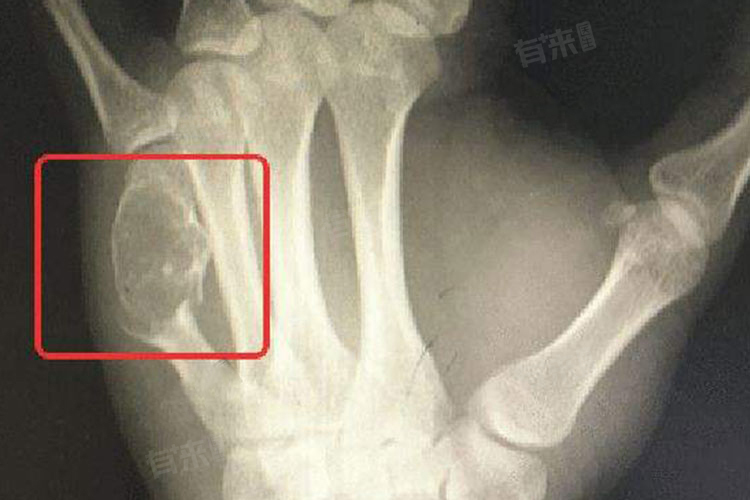

3、慢性炎症刺激:长期存在的骨髓炎、骨结核等慢性炎症,会使局部组织反复经历损伤与修复的过程。在这个过程中,细胞的增殖活动变得异常活跃,而细胞在进行DNA复制时,由于频繁的分裂活动,更容易出现错误,导致基因突变。这些突变的细胞在长期的炎症环境中逐渐积累,最终有可能转变为癌细胞,引发骨癌。